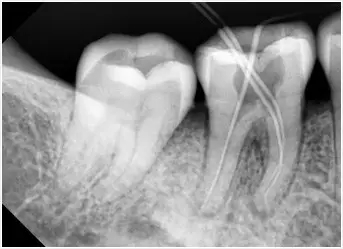

1.拍片 2.開髓 3.確定根管長度

4.根管預備 5.根管衝(chong) 洗消毒 6.根管充填